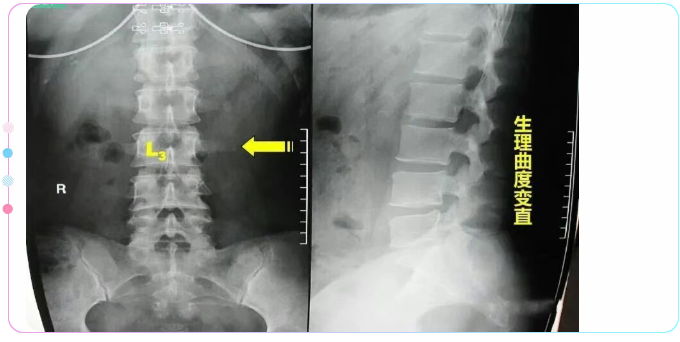

腰椎一共有五个,正常腰椎呈生理性前凸,第3腰椎位于前凸的顶部,腰椎在传导重力时,常是以第3腰椎为其活动中心,故成为腰椎前屈、后伸、左右旋转活动的枢纽。因此,两侧横突所受的牵拉应力最大。在生长发育过程中,受拉应力最大的横突其生长速度也最快。腰三横突位于肋弓与髂嵴之间,横突向后成30度角左右,向前倾斜15度左右,近尖部骨面增厚粗糙。

第三腰椎横突比其他腰椎的后伸曲度大,向侧方延伸最长,位于腰椎中部,两侧腰椎横突联线形成以第三腰椎横突尖为顶点的纵长菱形。第一、二腰椎横突外侧有下部肋骨覆盖,第四、五腰椎横突深居于髂骨内侧,只有第三腰椎横突缺乏肋骨及髂骨保护,因而易受损害。

第三腰椎位于腰前凸曲线之顶点,背阔肌的髂腰部分纤维止于第三腰椎横突,腰大肌的部分肌纤维也止于此处,骶棘肌的一部分肌纤维也止于此,因此,第三腰椎成了腰椎的活动中心,起到了类似接力站的作用,为腰椎屈、伸、侧弯及旋体的枢纽,所受的杠杆作用最大。而第三腰椎横突更是受力点。由于第三腰椎横突较长,以致附着于此处的肌肉、筋膜、韧带能有效地保持脊柱的稳定性及正常的活动。较长的横突又能增强肌肉的杠杆作用,肌肉收缩牵拉机会多,拉力最大,当这些组织异常收缩时,横突末端首当其冲。这种解剖特点构成末端易受损伤的基础,往往因劳损而引起横突末端周围的纤维织炎。横突越长,发病率越高,以单侧多见。